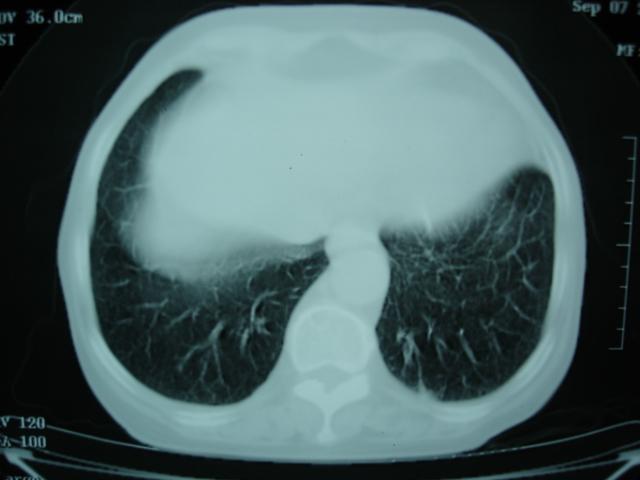

以下是引用卜一在2009-9-7 19:51:00的发言:[br][br] 1 左侧胸内甲状腺占位-多考虑甲状腺腺瘤! 2、左肺门占位-建议增强扫描以便明确性质。 3 慢支并感染! [br]

以下是引用shibing在2009-9-7 20:40:00的发言:[br]左侧胸内甲状腺占位-多考虑甲状腺腺瘤! 2、左肺门占位-建议增强扫描以便明确性质。 3 慢支并感染! [br]